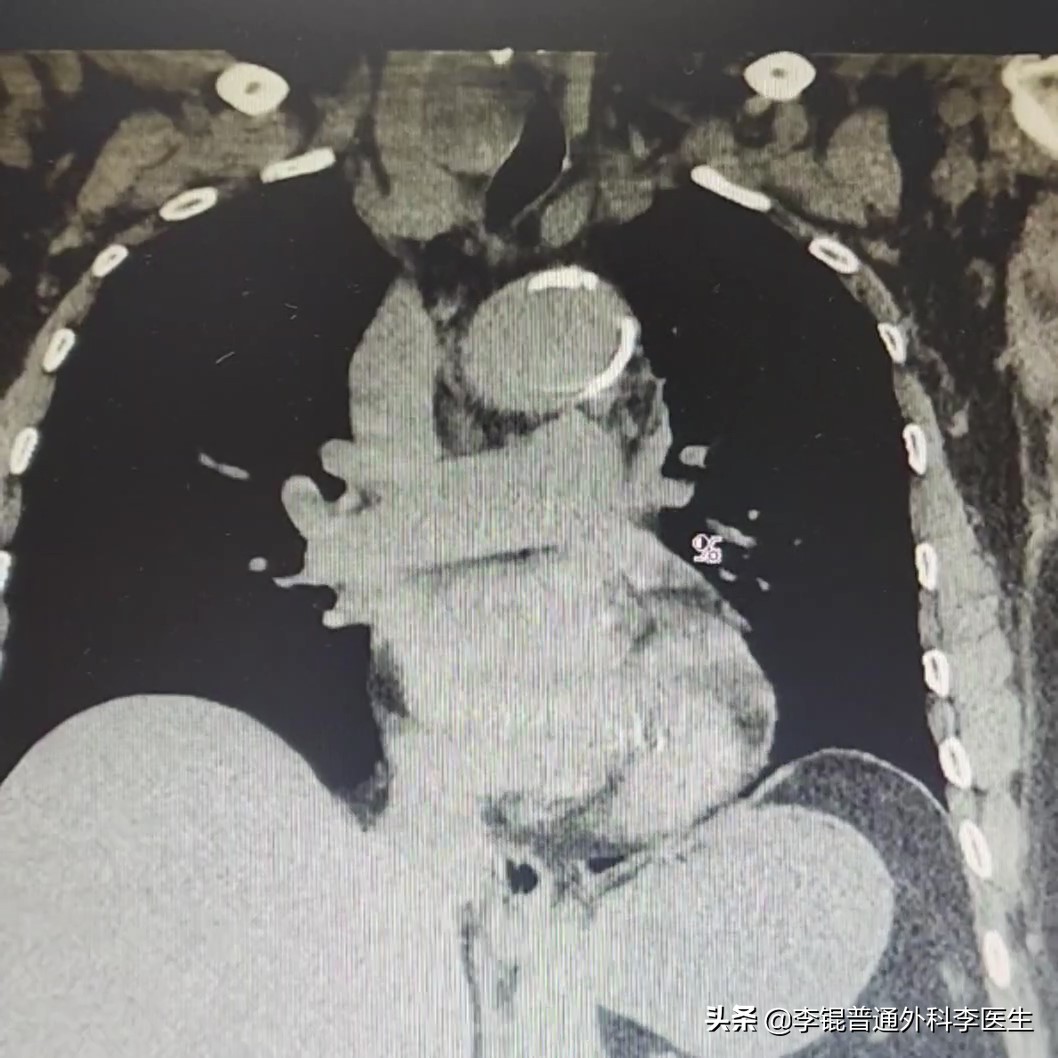

接连看了不同时间的CT检查,这个情况对比看起来会有个一个明显的加重。在CT上一侧的甲状腺有一个明显增大的结节并将气管挤到了一边。

这种情况其实很多老人都会出现,因为甲状腺疾病很常见,良性的甲状腺疾病可能十几年甚至几十年才出现症状,经过几十年的生长之后,甲状腺结节往往都很大了,对气管造成压迫,这时候由于气管被压了,痰就不容易咳出,积在肺里,细菌感染了就成了肺炎了。

这时候,往往需要进行手术治疗,切除肿大的甲状腺腺体和结节来缓解气管受到的压迫,让变形或者受压的气管通畅。